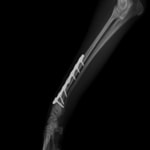

ペルシャ猫 11ヶ月齢 雄

他院にて左大腿骨遠位の成長板骨折(salter-harrisⅠ型)が認められており、治療相談を目的として来院。当院にて、キルシュナーワイヤーを用いたピンニングにより骨折部位の整復を行いました。術後の経過は良好で、現在も経過観察中です。

術前レントゲン

術後レントゲン